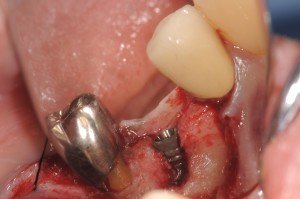

手前の部位は、頬側に骨欠損があったために、インプラントベッドを形成したら裂開ができたので、Bio-ossとBio-guideでGBRを行いましたが、術前のCTにより確認できていたので、想定内のオペでした。

7番部位は、1回法でヒーリングアバットを歯肉縁上にだして、5番部位は完全埋入2回法のオペです。

頬側にこの程度の、裂開が生じました。

バイオスとバイオガイドの黄金コンビです。

術後の状態ですが、綺麗です。

埋め込みのポジションも理想的です。